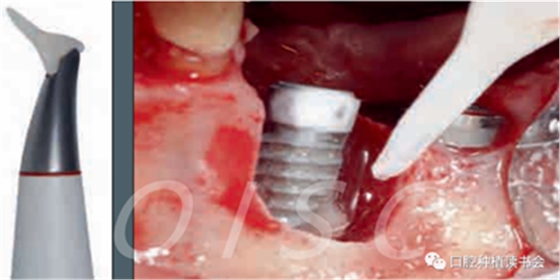

單純使用激光或噴砂對種植體周圍炎進行非手術治療效果不佳;研究表明化學療法和機械清創(chuàng)作用也不大;使用光動力療法治療種植體周圍炎的嘗試也沒有取得成功(圖3)。因此,我們可以確認:非手術治療的方法并不能阻止種植體周圍炎病情的發(fā)展

圖3 手術中使用噴砂裝置清潔暴露的種植體表面